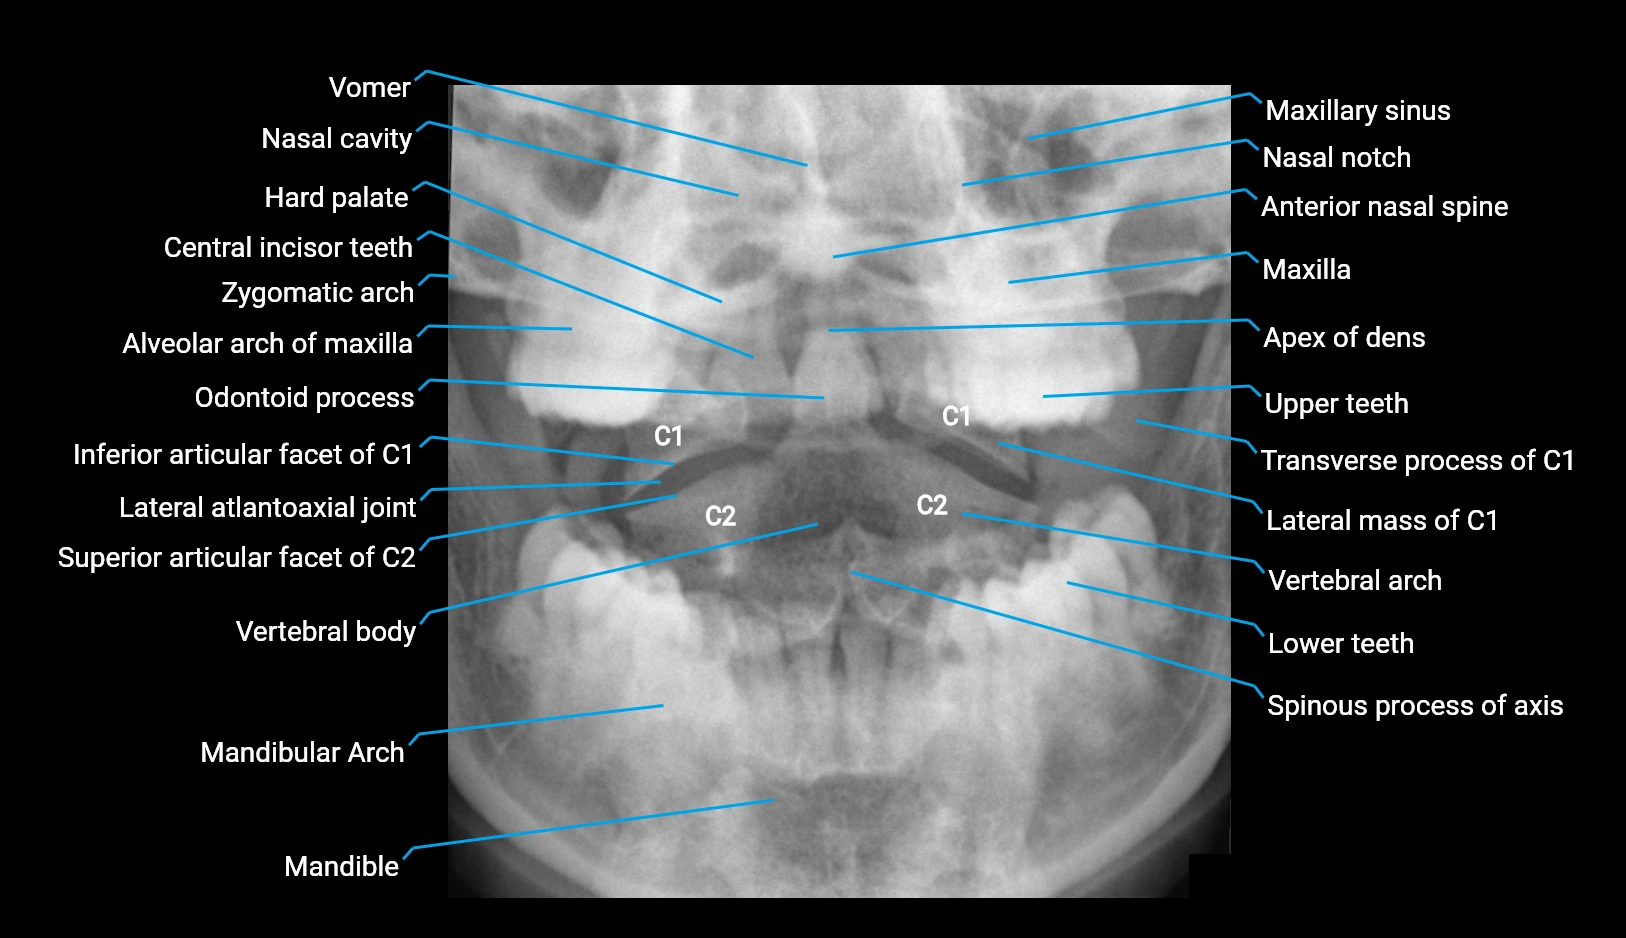

X-ray appearance

Spine radiographs (AP / lateral views):

• Annular epiphysis: Thin, linear bony rim along vertebral endplate margins

• Appearance: Smooth, well-corticated ring

• Age dependence: More conspicuous in children and adolescents

• Fusion: Disappears after complete fusion with vertebral body